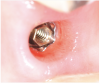

Tissue integration also depends on the surface properties of the materials in contact with peri-implant tissues, such as the surface energy and the decontamination and sterilization of the surfaces. Customized Computer-Aided Design/Computer-Aided Manufacturing (CAD/CAM) titanium and zirconia abutments may be fabricated using multiple technical procedures, all of which inevitably contaminate the surfaces of the materials, thus potentially compromising soft tissue integration and adherence.32 In vitro results have suggested that the decontamination of abutment surfaces is important for early fibroblast adherence and may improve the biological integration of peri-implant soft tissues.29 Ideally, abutments should have a surface that is completely decontaminated and sterilized, so as to allow for tight soft tissue adherence and integration in the subcritical and critical zones to support peri-implant tissues as well as create an effective soft-tissue seal/defense area against bacterial microorganisms. To achieve the best clinical performance in terms of soft tissue adherence, stock final abutments that are completely decontaminated and sterilized, with surface chemistry that boosts their biological response, should be the first choice (Figure 3 and Figure 4). These abutments are available in multiple heights, which should be selected based on the implant site, the vertical soft tissue thickness, and the esthetic expectations.

The critical contour should be designed to correctly support the soft tissues, conditioning and scalloping the pink esthetics. The height of the aCA should range from 2 to 2.5 mm (Figure 2), depending on the esthetic demands of the individual clinical case. In this area, particularly in the most coronal portion, the cleanability of the abutment is crucial to reduce the risk of contamination, and therefore a thoroughly polished surface with mirror-like appearance is necessary. This is particularly important in patients with poor or suboptimal oral hygiene, with a history of periodontal disease, or who smoke.